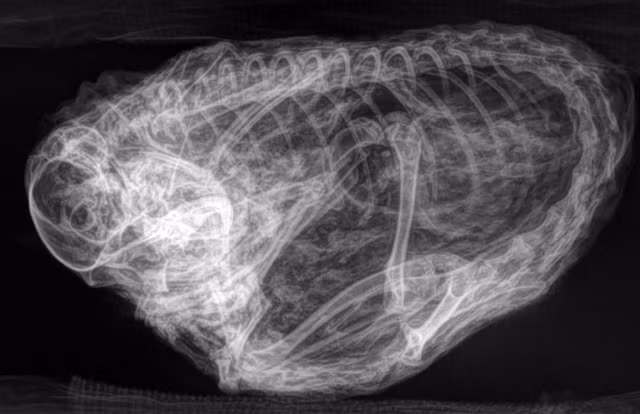

Xác ướp quái thú này khi chụp X-quang khiến các nhà khoa học vô cùng phấn khích.

Ban đầu, các nhà khoa học không thể nhận biết hình dạng của xác ướp. Bề ngoài của nó phủ một lớp lông màu nâu vàng, có kích thước tương đương quả bưởi, với đôi tay có vuốt nhọn.

Sau khi chụp X-quang, họ nhận ra đó là một con sóc đất Bắc Cực cổ đại thuộc chi Urocitellus parryii. Điều đặc biệt là nó giống với sóc đất Bắc Cực hiện đại. Sóc này sống trên địa hình Bắc Cực ở cả hai bên eo biển Bering.